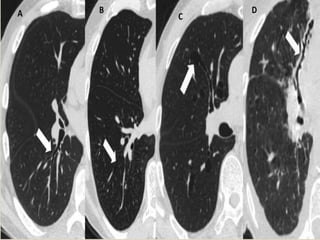

Congenital stenosis of left mainstem bronchus. Transverse images show

stenosis (arrow, A), distal bronchiectasis, and mucoid impaction (arrows, B).

A B